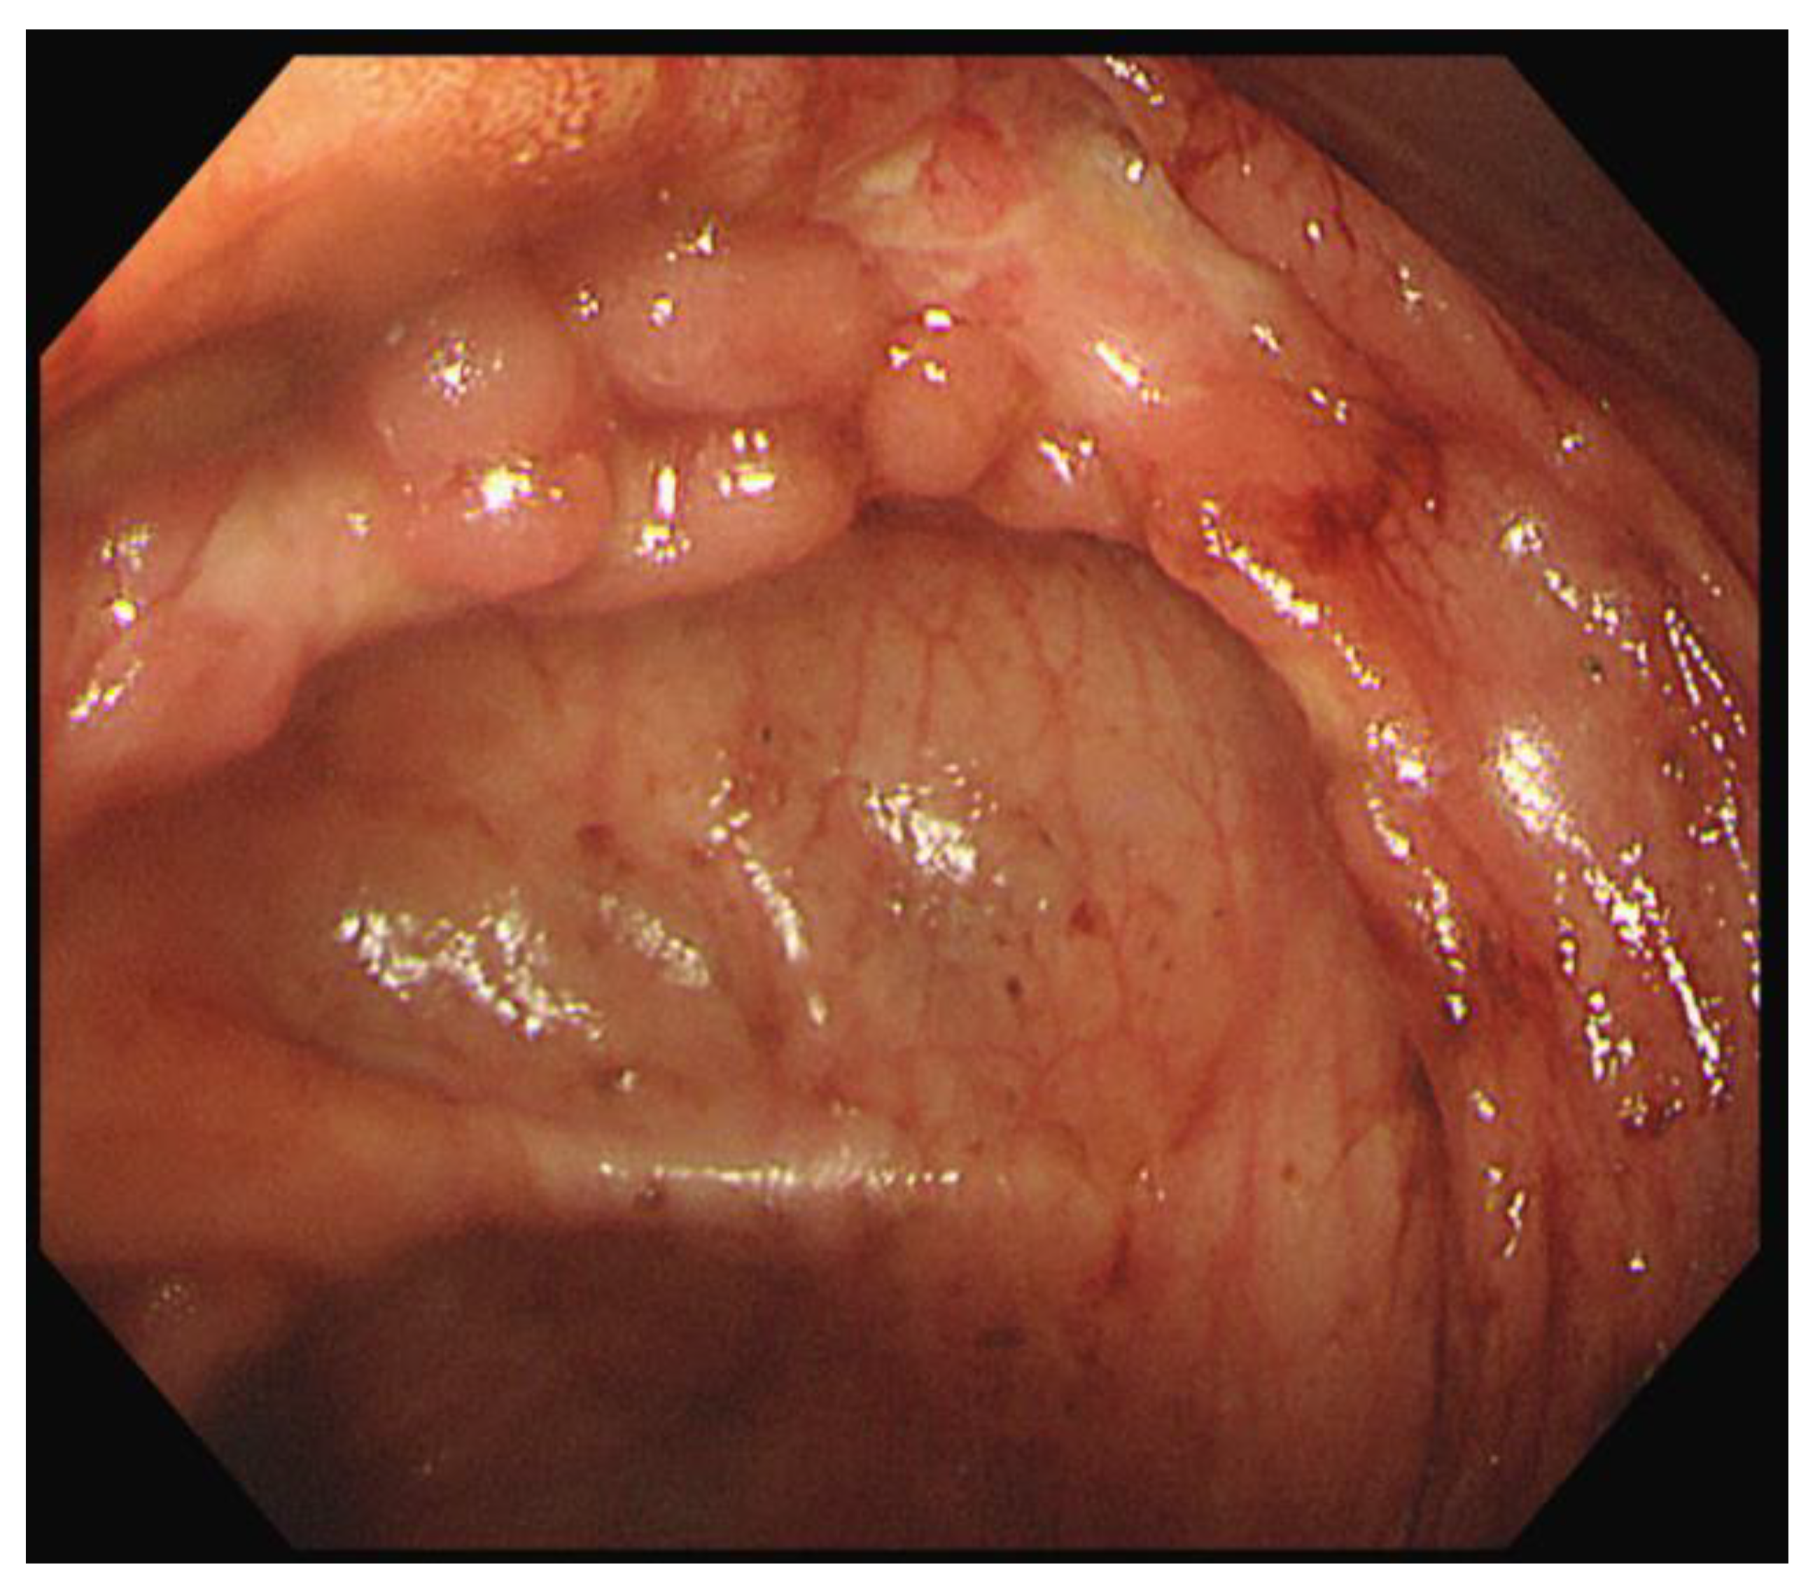

On the third day in the ICU, the patient had massive hematochezia (900 cc), which was the first episode of bloody stools. Vital signs were stable, and no sources of acute bleeding, such as extravasation or pseudoaneurysms, were observed on CT. On colonoscopy, ulcerations were observed in the distal terminal ileum and ileocecal valve. Although observation of the colonic mucosa was limited to blood, there was no focus of active bleeding (Figure 3).

Figure 3.

Initial endoscopic findings revealed ulcerations around the ileocecal valve.